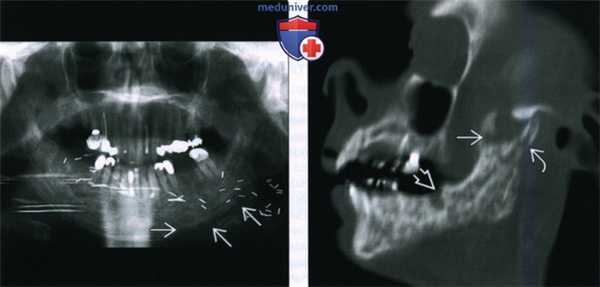

(Слева) На панорамной дентальной рентгенограмме у пациента, которому ранее было выполнено оперативное вмешательство и осуществлялась лучевая терапия полости рта, определяется диффузное утолщение и остеосклероз нижней челюсти, утолщение и деформация трабекул, нарушение дифференцировки кортикальной пластинки в области нижнего края нижней челюсти слева.

(Справа) При сагиттальной КТ (по углом) определяются множественные неоднородные «просветления» в кости, нарушение целостности кортикального слоя, утолщение и склероз трабекул и кортикальной пластинки. Обратите внимание на глубокую «лунку», оставшуюся после экстракции моляра. Определяется также фрагментация венечного отростка и шейки мыщелка.